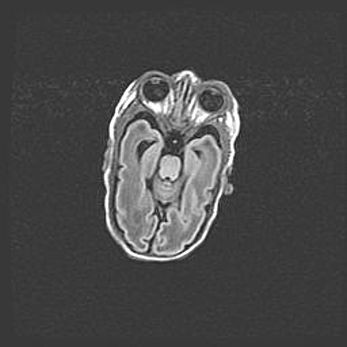

Неполная лизэнцефалия (пахигирия). Открытая гидроцефалия.

Возраст: 17 дней

Вес: 3110 г

Пол: мужской

Окружность головы: 33,5 см

Срок гестации: 35-36 недель

Лизэнцефалия—недоразвитие корковой пластинки и мозговых извилин в результате нарушения миграции нейронов коры. Поверхность мозговых полушарий гладкая. Микроскопически выявляется отсутствие нормальных слоев коры и скопление групп нейронов в подкорковом белом веществе.

Пахигирия—уменьшение числа вторичных извилин. В пораженном полушарии нервные клетки образуют толстый недифференцированный слой с неправильно расположенными нервными волокнами и группами гетеротопных клеток. Нервные клетки незрелые. Белое вещество истончено. При этом нередко аномально развит корково-спинномозговой путь.